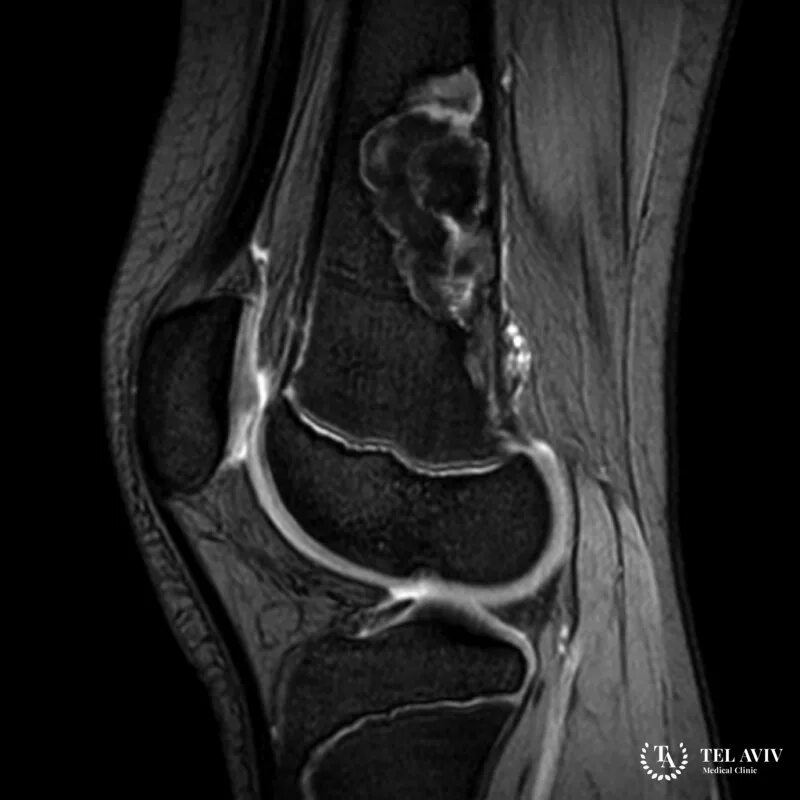

Фиброма кт